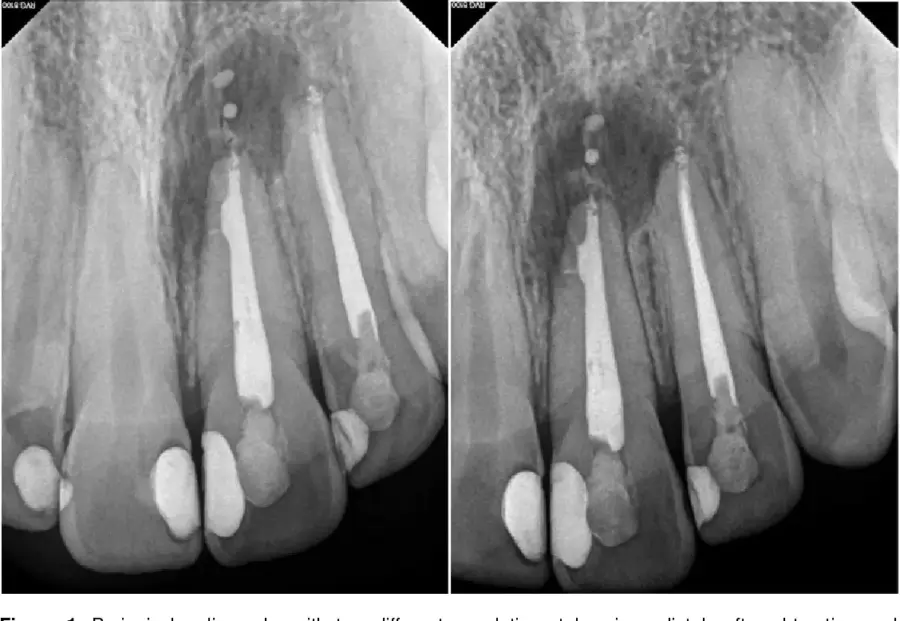

Chiều dài trám bít và kiểm soát chóp

Chiều dài trám bít là một trong những yếu tố quan trọng phản ánh chất lượng điều trị lần đầu. Trám ngắn để lại vùng chóp chưa được làm sạch, tạo điều kiện cho vi khuẩn tồn tại và phát triển. Trám quá chóp có thể gây kích thích mô quanh chóp, làm kéo dài quá trình lành thương. Những ca trám bít đúng chiều dài làm việc, kiểm soát tốt vùng chóp thường có tiên lượng retreatment thuận lợi hơn. Điều này cho thấy retreatment không chỉ “sửa lỗi”, mà còn phụ thuộc vào mức độ sai sót ban đầu.

Độ kín khít của hệ thống trám bít

Khoảng rỗng trong gutta-percha, sealer tan rã hoặc trám bít không đồng nhất đều tạo điều kiện cho vi khuẩn tái xâm nhập. Trong điều trị nội nha lại, các vùng này thường chứa biofilm cũ, khó loại bỏ hoàn toàn. Nếu không làm sạch triệt để, việc trám bít lại sẽ không mang lại hiệu quả sinh học lâu dài. Do đó, đánh giá phim X-quang và CBCT trước điều trị là bước không thể bỏ qua. Đây cũng là cơ sở để tiên lượng và lựa chọn chiến lược điều trị phù hợp.